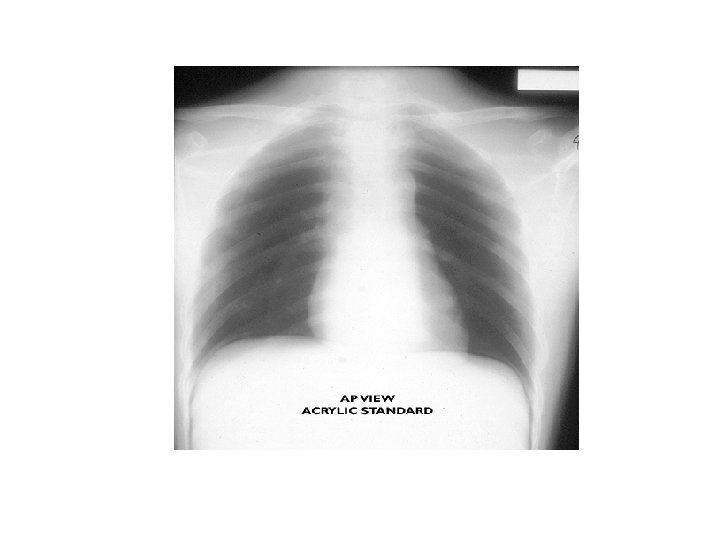

Göğüs • İns; • Palp; • Osk; Ön, arka ve yan duvarda yaralanma Künt ve penetran yaralar, cilt altı amfizem, hassasiyet, krepitasyon Solunum sesleri ve kalp sesleri X-Ray

Travmada Acil Radyoloji • Lateral servikal (C 1 -7, T 1) • AP akciğer • AP pelvis * Servikal AP ve odontoid * Yatak başı USG * BBT